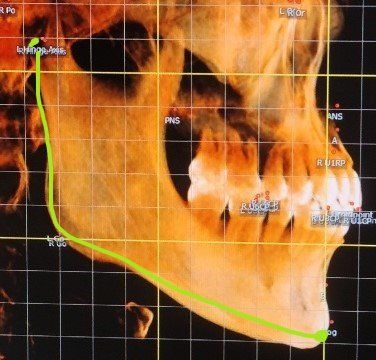

-턱의 길이를 잴때 귀밑부터 ㄴ자로 꺾어지는 곳, 다시거기서부터 턱끝까지의 길이의 합이 총 턱길이가되나요? 정확히 시작점이 귀밑인지 귀윗끝부터인지... 어디서부터 재야할까요?

-턱의 총길이 제가표시한 곳이 맞나요??

4.턱의 총길이 제가표시한 곳이 맞나요??

네 수직은 하악의 하악지(ramus)길이이며 아래부분은 턱의 길이라고 생각하시면될것같습니다.

일단 현재 ceph. 사진에 표시된 것으로 하악턱의 과성장 등을 파악하지 않습니다. 현재 사진에서 여러가지 계측점을 찍고 그에 따라 검사를 하게 되며 정상범위 및 표준범위는 여러가지 계측점에 따라 상대적으로 평가하기 때문에 절대적인 기준이라는 것이 없습니다. 즉 사람에 따라서 지금의 턱 길이 정도라도 상악이 발달하면 이는 주걱턱이 되지 않는 것처럼 현재 턱 길이만으로는 주걱턱 및 하악 과성장이라고 하지 않습니다.